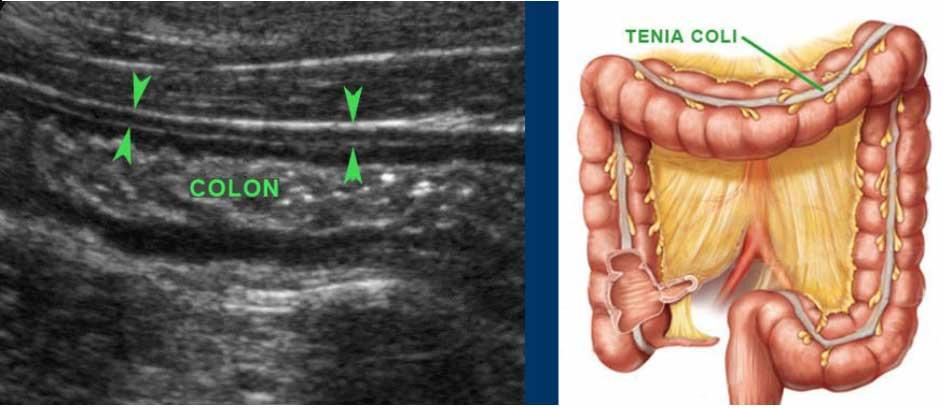

Colon

Hình ảnh dọc (trái) và ngang (phải) của đại tràng sigma rỗng ở bệnh nhân gầy.

Trong hình ảnh mặt cắt ngang, ba vùng dày lên cục bộ của lớp cơ (đầu mũi tên) đại diện cho ba dải cơ dọc kết tràng (đầu mũi tên).

Normal colon wall thickness during compression is 3-4 mms.

Bóng lưng âm học của phân cản trở việc hiển thị siêu âm thành sau (bên trái).

Đại tràng được phân biệt với ruột non bởi vị trí, nội dung phân, nhu động thưa và lớp cơ ngoài dày với ba dải cơ dọc (tenia coli).

Lớp cơ của đại tràng sigma có thể thay đổi đáng kể về độ dày, chủ yếu do sự co bóp.